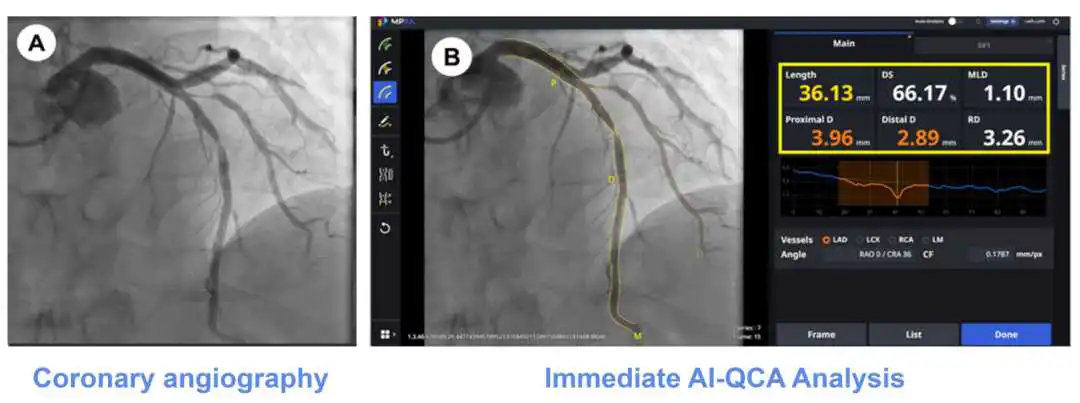

对于AI-QCA组的患者,在PCI过程中,使用AI-QCA进行实时分析(图1)。该系统能够自动识别并量化病变的严重性和特征,提供关于支架尺寸、长度和放置位置的推荐。AI-QCA系统会输出一个详细的治疗建议报告,包括最佳视图选择、预期的支架位置以及建议的扩张策略。操作医生根据这些数据进行决策,优化PCI的执行。对于OCT组的患者,使用OCT作为主要的指导工具。OCT提供高分辨率的血管内成像,帮助医生精确评估病变性质和决定支架的最优位置。OCT操作中,医生会实时观察血管内的图像,据此进行决策处理。OCT图像帮助识别病变的精确长度、血管直径和存在的钙化情况,从而选择合适的支架并进行精确的放置。